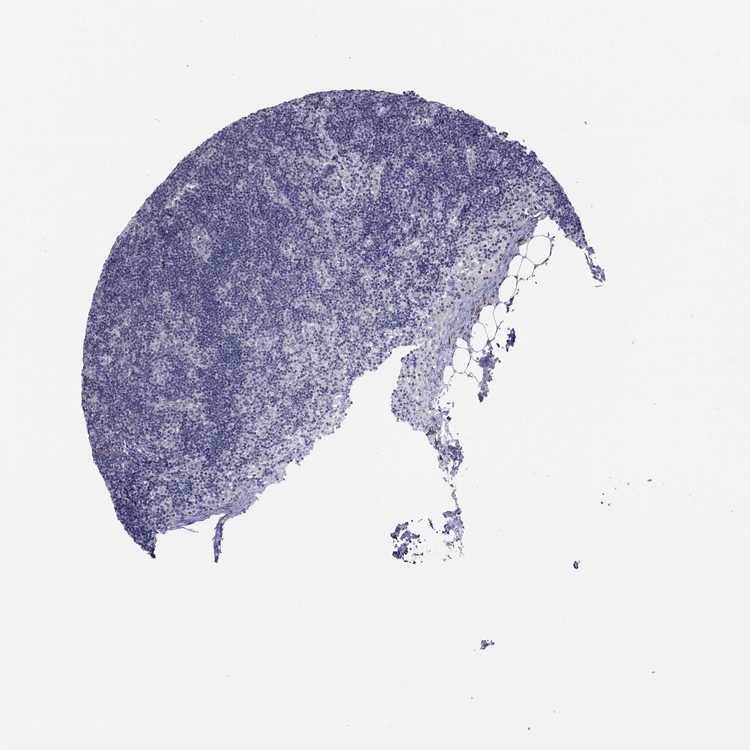

TISSUE PRIMARY DATA LYMPH NODE Show tissue menu

LYMPH NODE - Antibody stainingi

Antibody staining in the annotated cell types in the current human tissue is reported as not detected, low, medium, or high, based on conventional immunohistochemistry profiling in selected tissues. This score is based on the combination of the staining intensity and fraction of stained cells.

Each image is clickable and will lead to virtual microscopy that enables deeper exploration of all samples and also displays staining intensity scores, fraction scores and subcellular localization as well as patient and tissue information for each sample.

Antibody HPA062531

Non-germinal center cells Not detected